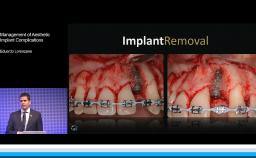

Management of Esthetic Implant Complications: Prosthetic Aspects

This lecture discusses various types of prosthesis-related implant complications that can occur in the esthetic zone. Management of esthetic implant complications are discussed via numerous case presentations. A review of the literature is presented to highlight the most common issues and causes of complications. Advice, clinical recommendations, and alternative treatment options are proposed to reduce the risk of complications in daily clinical practice.